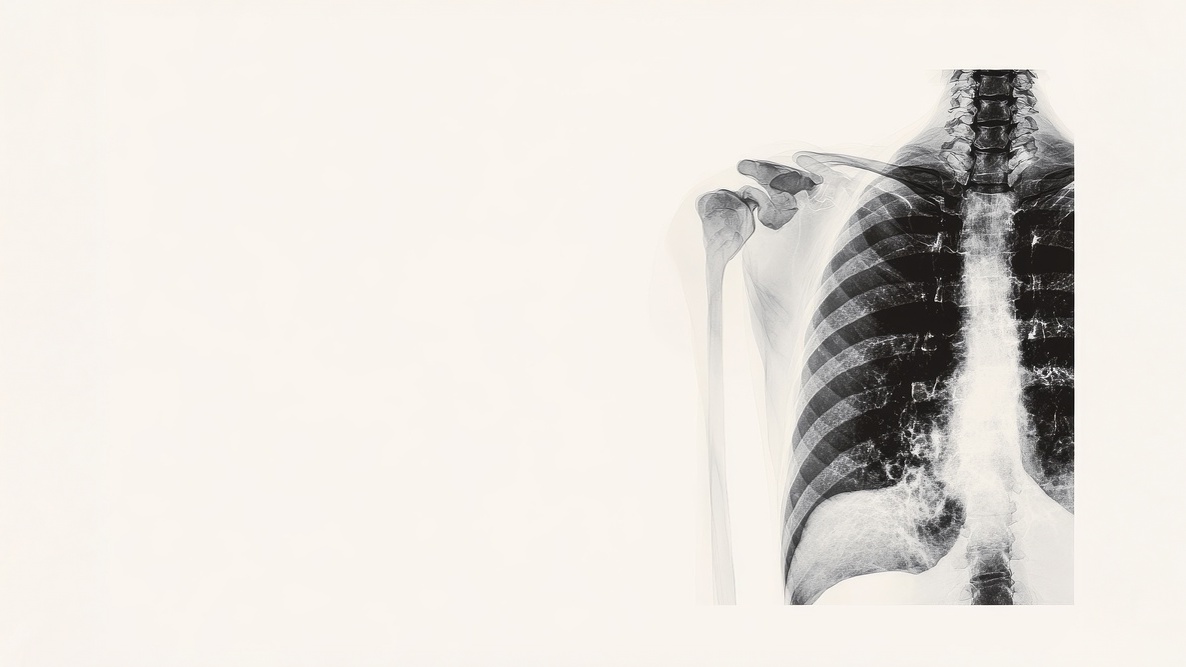

A fratura de costelas é um evento relativamente comum em traumas torácicos contusos, respondendo por cerca de 10% dos casos nesse tipo de trauma podendo atingir até 50% em eventos mais graves. Estima-se que cerca de 1/3 dos pacientes que sobrevivem a traumatismos torácicos graves irão precisar de algum tipo de reabilitação por até 6 meses após o acidente.

O tórax instável foi uma das grandes indicações de estabilização cirúrgica. Nesse último consenso da CWIS foi definido como a presença de fratura em 3 ou mais arcos costais consecutivos em dois ou mais locais distintos, clinicamente demonstrado por movimento paradoxal da parede torácica, com interrupção da respiração e redução da capacidade pulmonar.

Fraturas bicorticais em 3 ou mais costelas do mesmo lado com deslocamento superior 50% correspondem a outra indicação de estabilização cirúrgica. Um estudo recente, conduzido pela própria CWIS (CWIS NON-FLAIL) identificou melhores resultados em pacientes com fraturas bicorticais severas que foram submetidos a estabilização cirúrgica.